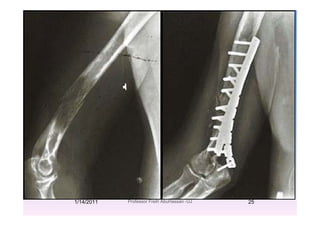

Lower Humeral Shaft LesionLower Humeral Shaft Lesion

Dual reconstruction plates with PMMA

N.B: Olecranon osteotomy nonunion

when patients are radiated.

1/14/2011 24Professor Freih AbuHassan -UJ

1/14/2011 25Professor Freih AbuHassan -UJ

E t i l i th j i tExtensive lesions near the joint

Total elbow arthroplastyTotal elbow arthroplasty